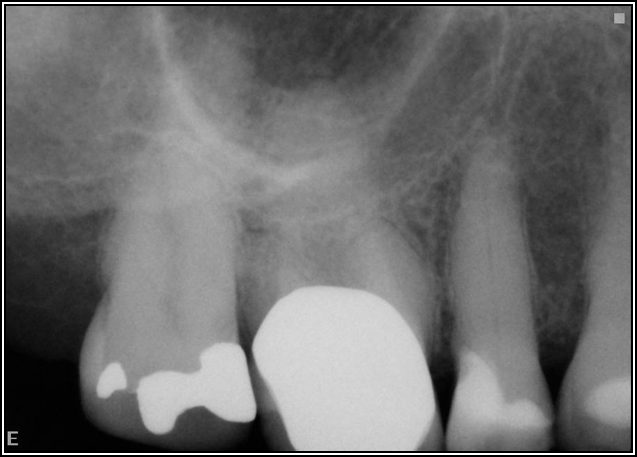

Occlusion is one of the most overlooked areas in endodontics; however, other than remaining structure, it is the most important factor.7 Patients who are heavy bruxers can cause the need for a root canal from the lateral forces. Patients who clench pose a different challenge with apical forces, yet the damage from both can be the same. Figure 7 shows a patient with bruxism. The patient had pain in response to hot and cold stimulus, and the clinicians needed a bitewing to determine which tooth was causing the pain. From the periapical (PA), it was clear that tooth No. 2 had a large problem, No. 3 had a crown, and No. 4 had a large restoration. Any of the three may have been the source of the problem.

With the bitewing shown in Figure 8, it became clear there was gross decay in tooth No. 3 that could not be seen on the PA, and there was a periodontal defect, a pulp stone, in No. 2. There was also a class V lesion revealing the bruxism, flat occlusion, multiple restorations in No. 30, a post in No. 31, and decay on No. 2 as well. The post in No. 31 was useless because when a post is placed, it must be the right length, width, and size. If the post is too short, there will be a greater fulcrum and the tooth will break. If it is too long, the clinician can break it by wedging it. If it is too short, it will not hurt the tooth, but it will not provide any valuable function. It is overall preferable to do posts in teeth having just single restorations rather than abutments for bridges because those teeth are already under greater force. If the technique is not performed correctly, iatrogenic issues may result.

Fig 8. Bitewing revealed decay and other problems.

Figure 8